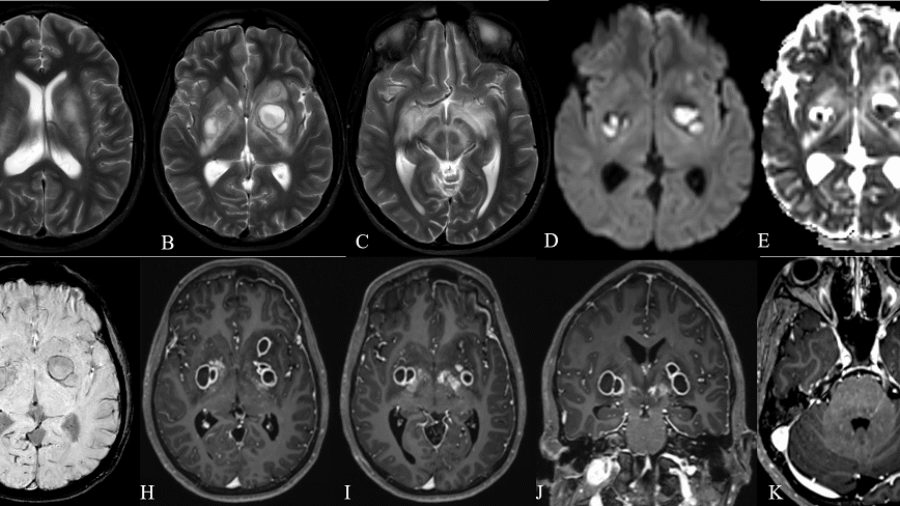

A 21 year old male was brought for evaluation of fever since 45 days associated with holocranial headache for 30 days and altered sensorium for 20 days .Working clinical diagnosis of chronic meningoencephalitis was made for which cross sectional imaging was requested.